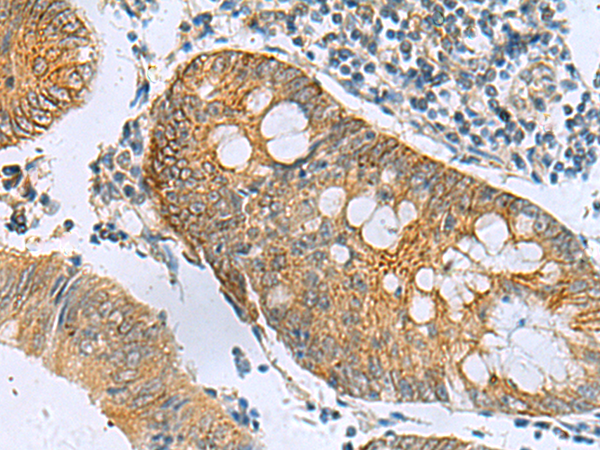

分类: 科研抗体货号: P10315别名: NDGOA; PARK5; PGP95; SPG79; PGP9.5; Uch-L1; HEL-117; PGP 9.5; HEL-S-53应用: WB,IHC反应种属: Human, Mouse, Rat